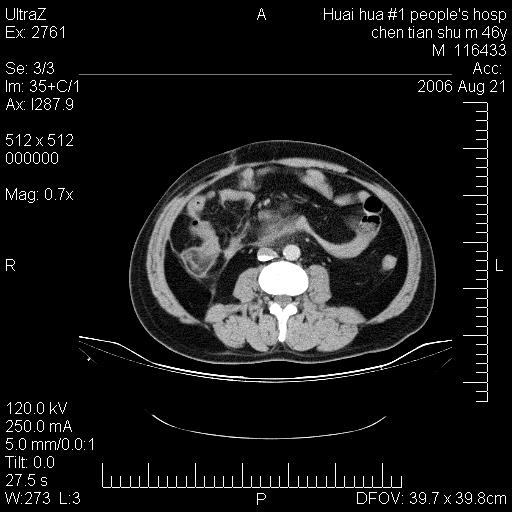

患者,男,46y。腹痛2月,消瘦。

十二指肠水平段占位,考虑间质瘤或平滑肌瘤。

肿块较大,腹膜后占位,境界欠清,周边脂肪密度较高呈条状影,有没有脂肪肉瘤可能,

缺少完整的三期图像。考虑肠系膜脂膜炎mp(肿块型)。

鉴别:间质瘤(这么大而无囊变不可思议)、平滑肌瘤/肉瘤、淋巴瘤、类癌,脂肪类肿瘤、转移瘤等。

十二指肠水平段占位,考虑间质瘤。

首先考虑小肠间质瘤。

十二指肠水平段软组织密度占位,考虑间质瘤可能性大。

腹膜后占位,境界欠清,考虑来源于十二指肠病变,间质瘤或平滑肌肉瘤可能性大。建议活检。

手术病理结果:原发性小肠恶性淋巴瘤(primary gastrointestinal lymphoma,pgil)是原发于胃肠的淋巴网织系统的恶性肿瘤,在结外淋巴瘤中居第一位,该病少见,临床无特异性,诊断困难,术前主要依靠影像学诊断。胃肠道本身具有较丰富的淋巴组织,因而胃肠原发性淋巴瘤是结外淋巴瘤最常见的部位,文献报道约占胃肠道恶性肿瘤的1%~4%,其中胃约占50%~70%,小肠约占35%~70%,结肠约占4%~6%。影像检查在pgil的诊断及分期中有重要的作用,ct是很有价值的检查方法。

胃肠淋巴瘤病理特点:胃肠道原发性淋巴瘤起源于胃肠壁固有层和黏膜下层的淋巴组织即胃肠粘膜相关淋巴组织(malt),多为粘膜相关淋巴瘤。病理上通常为非霍奇金淋巴瘤,且决大多数来源于b淋巴细胞,很少见于霍奇金淋巴瘤。胃肠原发淋巴瘤比胃肠道癌的发病率要低的多,最常见于胃,其病因可能跟幽门螺杆菌感染有关。幽门螺杆菌能引起胃粘膜损害,引起炎性及免疫反应,淋巴细胞聚集并形成滤泡,可影响胃的正常生理功能,导致胃淋巴瘤的发生。单纯性小肠淋巴瘤是常见好发于回盲末端,受累的肠段较长,可单发、多发,甚至累及整个小肠。原发性大肠淋巴瘤罕见,以直肠和盲肠最多见。病变大体观可表现为胃肠腔内外的肿块,也可表现为从黏膜下到浆膜面肠壁的纵向浸润,并且常常伴有肠系膜淋巴结肿大。任何情况下,肿瘤几乎总是导致一定程度的肠壁增厚,可对称或不对称,病变与正常组织间常无明确分界,肠腔可狭窄、正常或动脉瘤样扩张,后者主要是肿瘤在肠壁内浸润,破坏肠壁内植物神经丛所致。以上改变成为ct检测病变的病理基础。

肠道淋巴瘤的ct表现分为4类

1) 壁内浸润型, (2)多发结节型, (3)肠系膜受累伴腔外肿块型(本型就是),(4)肿块型。